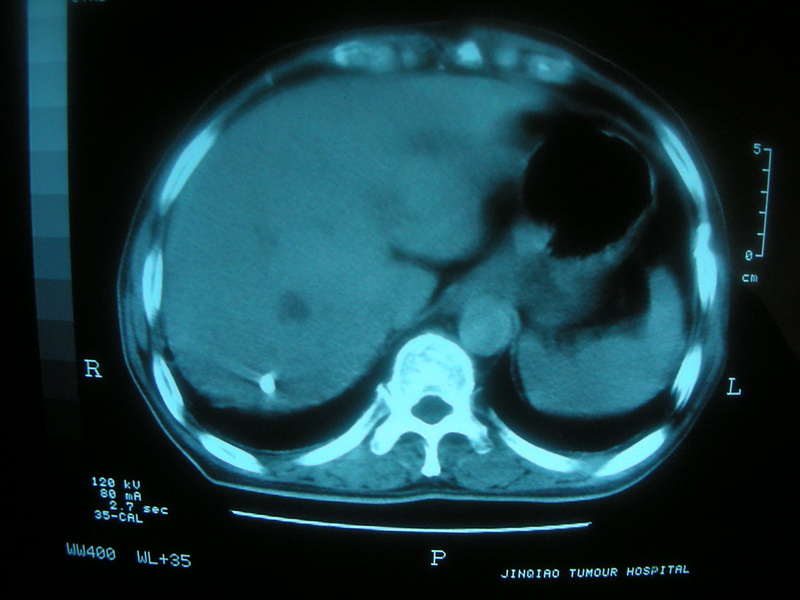

标题: CT11692:男,63岁,糖尿病史15年.抗炎治疗7天,病情 [打印本页]

标题: CT11692:男,63岁,糖尿病史15年.抗炎治疗7天,病情

请老师看看是结核还是炎症?

根据影像表现及临床符合结核感染。

双肺继发性肺结核伴感染!